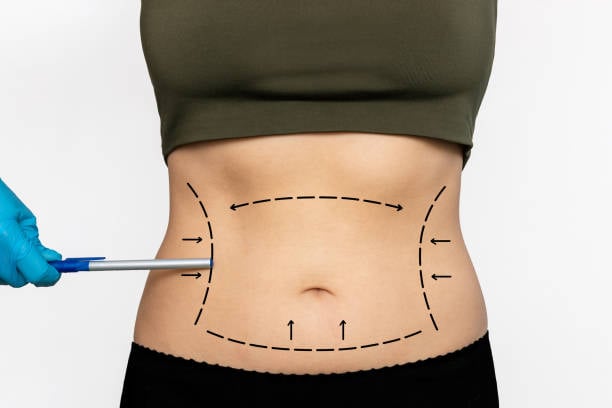

تعد عملية شفط الدهون في الرياض واحدة من الخيارات الرائجة لتحسين مظهر الجسم واستعادة الثقة بالنفس. تُقدم هذه العملية حلولًا فعالة للأشخاص الذين يسعون للتخلص من الدهون الزائدة في مناطق محددة من الجسم والتي قد لا تستجيب للحمية الغذائية أو التمارين الريا...

شفط الدهون هو إجراء جراحي تجميلي يستخدم للتخلص من الدهون الزائدة في مناطق معينة من الجسم التي يصعب التخلص منها عن طريق الرياضة أو النظام الغذائي. في الرياض، أصبح شفط الدهون خيارًا شائعًا للعديد من الأشخاص الذين يسعون لتحسين مظهرهم واستعادة ثقتهم بأنف...

عملية شفط الدهون في الرياض هي واحدة من أبرز الإجراءات التجميلية التي يسعى الكثيرون إلى إجرائها لتحقيق جسم أكثر تناسقًا ووزنًا مثاليًا. تُعد هذه العملية خيارًا مثاليًا للأشخاص الذين يعانون من تراكم الدهون في مناطق معينة من الجسم ولا يمكنهم التخلص منها...

شد البطن في الرياض هو الحل المثالي لأولئك الذين يسعون للحصول على بطن مشدود ومسطح. مع تقدم العمر أو بعد الحمل أو فقدان الوزن، قد يظهر التراكم الدهني أو الترهل في منطقة البطن، مما يسبب الإزعاج للكثيرين. في هذه المقالة، سنقدم لكِ كل ما تحتاجين معرفته عن...